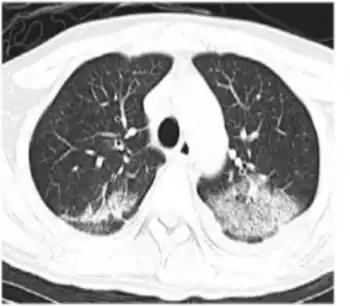

HHV-6B primary infection is the cause of the common childhood illness exanthema subitum (also known as roseola infantum or sixth disease). It is passed on from child to child. It is uncommon for adults to contract this disease as most people have had it by kindergarten, and once contracted, immunity arises and prevents future reinfection. Additionally, HHV-6B reactivation is common in transplant recipients, which can cause several clinical manifestations such as encephalitis, bone marrow suppression, and pneumonitis.[6]

The classical presentation of primary HHV-6b infection is as exanthema subitum (ES) or "roseola", featuring a high temperature followed by a rash. However, one study (1997) indicated that a rash is not a distinguishing feature of HHV-6 infection, with rates similar to non-HHV-6 infections (10–20% of febrile children in both groups). HHV-6 infections more frequently present with high temperatures (over 40C), at a rate of around two thirds compared to less than half in the non-HHV-6 patients. Similarly significant differences were seen in malaise, irritability, and tympanic membrane inflammation.[13]

Diagnosis for the virus, particularly HHV-6B, is vital for the patient because of the infection's adverse effects. Symptoms that point to this infection, such as rashes, go unnoticed in patients that receive antibiotics because they can be misinterpreted as a side-effect of the medicine.[13] HHV-6B is known to be associated with the childhood disease roseola infantum, as well as other illnesses caused by the infection. These include hepatitis, febrile convulsions, and encephalitis. Children who have exanthema subitum, caused by an HHV-6B infection, experience fevers lasting 3 to 5 days; rashes on the torso, neck, and face; and sometimes febrile convulsions, however, the symptoms are not always present together. Primary infections in adults are rare since most occurrences are in children. When the infection does occur for the first time in an adult the symptoms can be severe.